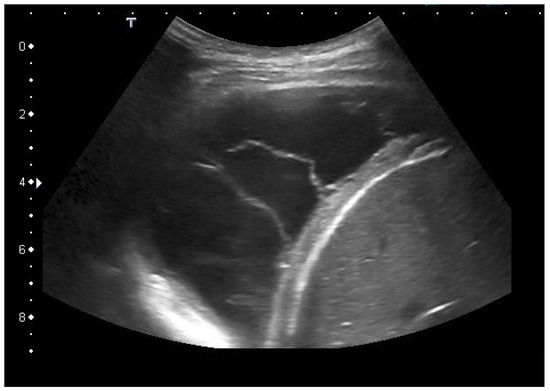

| Empyema | Hypoechoic thickened pleura, internal echos in the pleural effusion, hypoechoic pus, hyperechoic gas reflexes, fibrin strands, and chambering. In the phase of organization, thickened pleura, chambering of the pleural space. |

| Empyema necessitans | Exceeds the parietal pleura and infiltrates the surrounding soft tissue and chest wall muscles. |